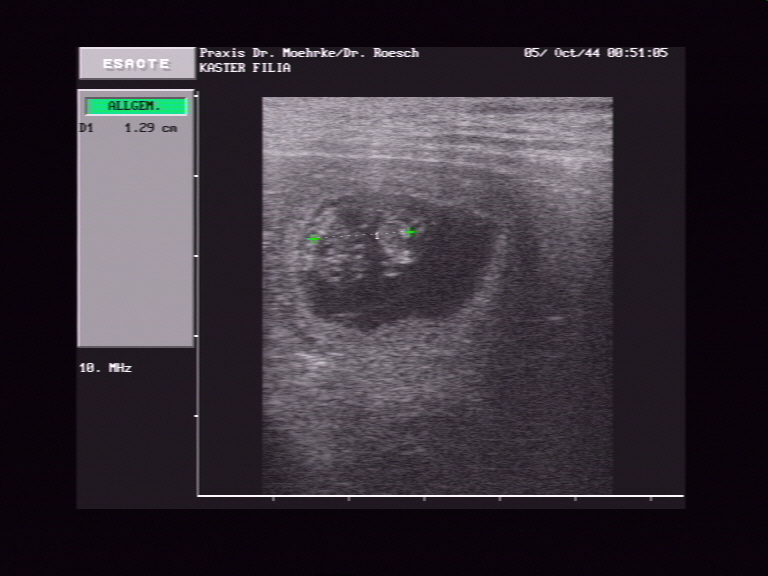

Ultraschall am 01.04.2009: Hurra, wir sind trächtig!

*   *

*Datum auf der Aufnahme stimmt leider nicht